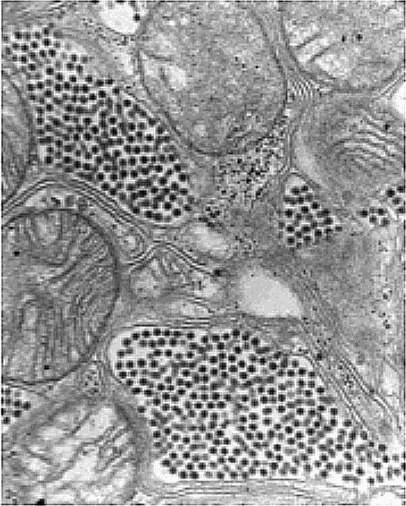

Гостиница вела с мышами нещадную войну, особенно после того, как в долине были зафиксированы случаи заболеваний, вызванных вирусом, переносчиком которого являются грызуны. Однако война в этом коттедже уже завершилась. Точнее, почти завершилась. Одинокая мышка ползла по ковру, трясясь всем своим телом. Внимание Дженны было полностью приковано к жуткой картине перед глазами, и она среагировала слишком медленно. Подчиняясь охотничьему инстинкту, Никко бросился вперед. – Никко, стой! Услышав команду хозяйки, лайка остановилась, но полудохлая мышка уже была у нее в зубах. Обернувшись, собака опустила хвост, понимая, что совершила какую-то оплошность. – Никко… Выронив мышку, пес виновато побрел к хозяйке, опустив морду и поджав хвост. Одной рукой оттолкнув Дженну назад, другой Дрейк захлопнул дверь. То, что затаилось внутри этой комнаты, было многократно страшнее любого вируса. Оставшийся за дверью Никко заскулил, умоляя, чтобы его выпустили. 09 часов 01 минута Лиза стояла в шлюзовой камере, дожидаясь, когда выровняется давление и можно будет открыть внутреннюю дверь, ведущую в лабораторный комплекс. За стенами слышался тихий стук капель дождя по металлической крыше ангара. Напомнивший молодой женщине о том, что время поджимает. По прогнозам местных метеорологов, мощный грозовой фронт продолжал наползать на регион. Пока что акры мертвой земли вокруг эпицентра оставались сухими, но было лишь вопросом времени, когда черные тучи прольются дождем над этим районом. Специальной группе было поручено оценить с помощью программы компьютерного моделирования, учитывающей топографические и геологические параметры, как далеко сможет распространиться зараза. Предварительные данные были пугающими. В настоящий момент Пейнтер проводил телеконференцию с участием различных местных и федеральных чиновников. Директор «Сигмы» стремился быть на шаг впереди катастрофы. К сожалению, от человека, прибывшего посреди ночи, пока что была одна только головная боль. Технический директор Управления анализов и тестов американской армии прилетел с испытательного полигона Дагуэй в штате Юта, где отрабатывались методы противодействия ядерной, химической и биологической угрозе. Всего за несколько часов он успел достать Пейнтера. Над внутренней дверью зажглась зеленая лампочка, и магнитный замок открылся. Приглушенный хлопок возвестил о выравнивании давления. Лиза вышла из шлюзовой камеры, радуясь возможности свалить все политические дрязги на своего жениха. Ей предстояла сложная задача, требующая полного ее внимания. Лиза оглянулась на карантинный бокс в дальнем конце ангара. Джошу поставили капельницу с диазепамом, и он снова уснул. Причина кратковременного приступа оставалась неизвестна, но, как выяснила Лиза, возможно, это было свидетельством того, что инфекция распространилась на центральную нервную систему. У нее перед глазами снова возник острый шип, глубоко вонзившийся в ногу. «Хочется надеяться, что я ошибаюсь…» И все же Лиза собиралась работать до тех пор, пока не появится полная уверенность. – Доктор Каммингс, вы вернулись… Фантастика! Голос прозвучал в наушнике, подключенном к рации. Обернувшись, Лиза увидела доктора Эдмунда Дента, вирусолога из ЦКЗ, стоящего у окна своей лаборатории. Он приветственно поднял руку – затем помахал Лизе, приглашая ее к себе. – Благодаря вашей работе нам, похоже, удалось добиться значительного прогресса в выделении заразной частицы, – продолжал Дент. – Как только мы узнали, что речь идет о чем-то столь крохотном, дело пошло гораздо быстрее. Но мне бы хотелось выслушать ваше мнение относительно того, что мы установили к настоящему времени. – Конечно, – ответила Лиза. Радуясь хоть какому-то продвижению вперед, она поспешила к маленькой шлюзовой камере, ведущей в лабораторию. Эта секция комплекса БСЛ-4 сияла нержавеющей сталью высокоскоростных центрифуг, масс-спектрометра, сверхточного микротома и криогенной камеры. Дополняли оборудование два мощных электронных микроскопа. Войдя в лабораторию, Лиза увидела еще одну фигуру в белом халате, склонившуюся к компьютерному монитору. Она узнала этого человека только тогда, когда он обернулся, и постаралась скрыть свое удивление. Это был доктор Реймонд Линдаль, технический директор УАТ. Судя по его лицу, скрытому маской, ему было лет пятьдесят с небольшим. Неестественно черные волосы, скорее всего, были подкрашены, чтобы скрыть седину, и то же самое можно было сказать про козлиную бородку. С самого своего появления здесь доктор Линдаль совал свой длинный нос во все работы центра, вынося скоропалительные заключения и требуя перемен, когда у него была такая возможность, – что, к огромному сожалению Пейнтера, бывало слишком часто. И вот теперь, судя по всему, Лизе предстояло разделить страдания своего жениха. Разумеется, этот человек имел полное право находиться здесь. Она знала, что доктор Линдаль является признанным специалистом в области генетики и биоинженерии. Однако талант породил в нем заносчивое высокомерие. – Доктор Дент, – натянуто промолвил Линдаль, – не думаю, что нам будет польза от познаний доктора Каммингс в медицине и психологии. Ее способности найдут лучшее применение, если она приложит их к клиническим исследованиям, сосредоточившись на изучении животных. Вирусолог не поддался на нажим, отчего Лиза зауважала его еще больше. Эдмунд был на десять лет младше Линдаля и стоял на богемных позициях, скорее всего, выкованных за годы, проведенные в Берклийском и Стэнфордском университетах. Хотя Лиза еще ни разу не видела его без защитного костюма, она всегда представляла его в сандалиях на босу ногу и линялой футболке. – Именно Лизина работа предопределила наш прогресс, – напомнил Линдалю Эдмунд. – И никогда не помешает свежий взгляд на проблему. К тому же, когда это мед в улье готовила всего одна-единственная пчела? У Линдаля вырвался обреченный вздох, но он не стал спорить. Эдмунд подкатил кресло к директору УАТ. – Лиза, позвольте ввести вас в курс дела. На предыдущем совещании я говорил о том, что, как мне показалось, нам удалось мельком взглянуть на то чудовище, с которым мы имеем здесь дело. Вот снимок поперечного среза альвеолы легкого инфицированной крысы. ![]() Лиза прильнула к экрану, изучая скопления крошечных частиц, плотно заполнивших маленькие воздушные клетки легкого. – Это определенно похоже на вирионы – внеклеточные вирусные частицы, – согласилась она. – Но я никогда не видела ничего столь крошечного. |